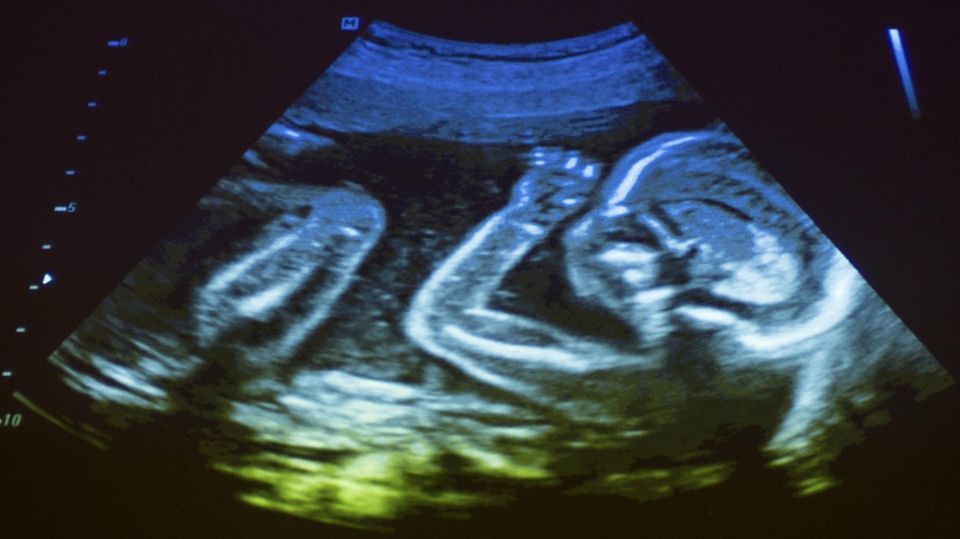

Dem Haptikforscher Prof. Dr. Martin Grunwald von der Universität Leipzig zufolge fasst sich jeder Mensch täglich unbewusst 400- bis 800-mal ins Gesicht. Das beginnt bereits im Mutterleib, wenn wir als Fötus noch im Fruchtwasser schwimmen. Wissenschaftlerinnen und Wissenschaftler konnten beobachten, dass sich die Selbstberührungen eines Fötus häufen, wenn die Mutter traurige oder emotionsgeladene Stimuli verarbeiten muss, also beispielsweise Filme oder Musik, und wenn sich das Stresslevel erhöht.